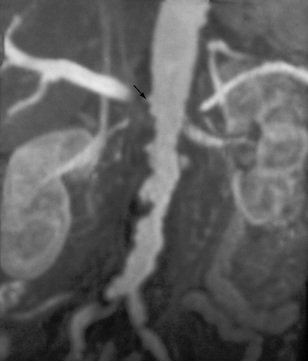

Renal artery stenosis can also be detected using magnetic resonance imaging, avoiding the use of potentially nephrotoxic contrast (Fig. 8.25).

image

Fig. 8.25 Magnetic resonance renal angiography demonstrating a tight stenosis at the origin of the right renal artery (arrow). The irregularity of the abdominal aorta is due to marked atheroma.